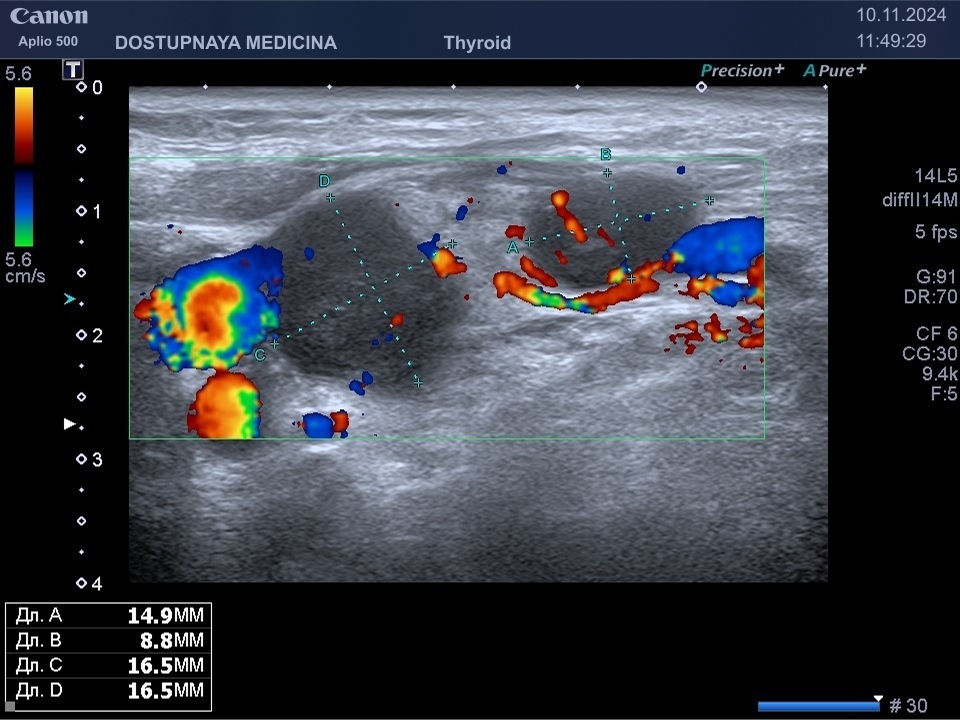

При ультразвуковом исследовании липосаркома чаще всего выглядит, как гипоэхогенное образование неправильной овальной формы, обычно с более пониженной эхогенностью (темнее) по сравнению с окружающей её подкожной жировой клетчаткой, с усиленным кровотоком в режиме ЦДК. В описании заключения важно так же отметить прилежит ли близко опухоль к какому-либо кровеносному сосуду или нерву.

Видно, что кровоток в образовании значительно усилен.

Более глубко расположенная опухоль в мягких тканях может оказаться рабдомиосаркомой. Это злокачественная опухоль, возникающая из поперечно-полосатой мышечной ткани. Наиболее часто встречается у детей и подростков. Симптомы её – болезненное уплотнение в области поражения, общая слабость и снижение веса, в некоторых случаях лихорадка. Миосаркомы обладают агрессивным ростом и быстрым метастазированием. Лечение миосарком хирургическое. Дополнительные методы лечения – это лучевая терапия и химиотерапия.

Опухоль верифицирована гистологически.